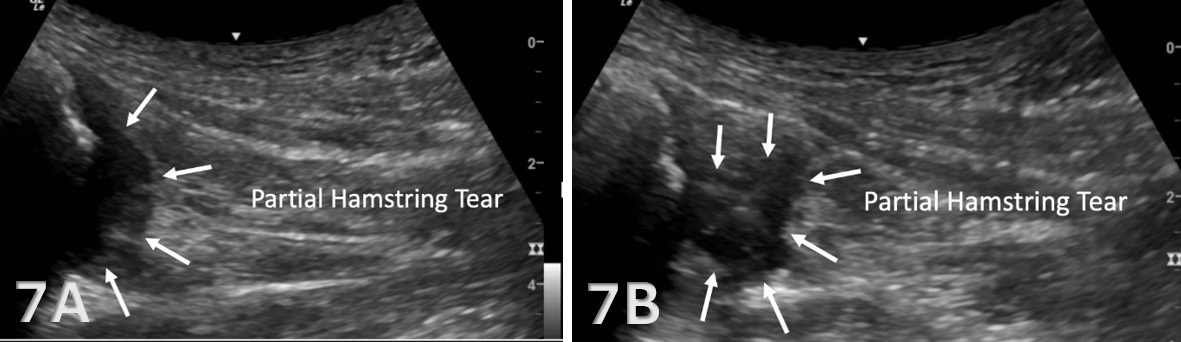

Pathologic Findings in Lateral Proximal Hamstring Tendon and Muscle Injury

Disruption of fibrillar pattern in partial tears and ruptures. Proximally, it is important to determine if the injury is a free-tendon injury or purely a myotendinous injury.20

Associated effusion.